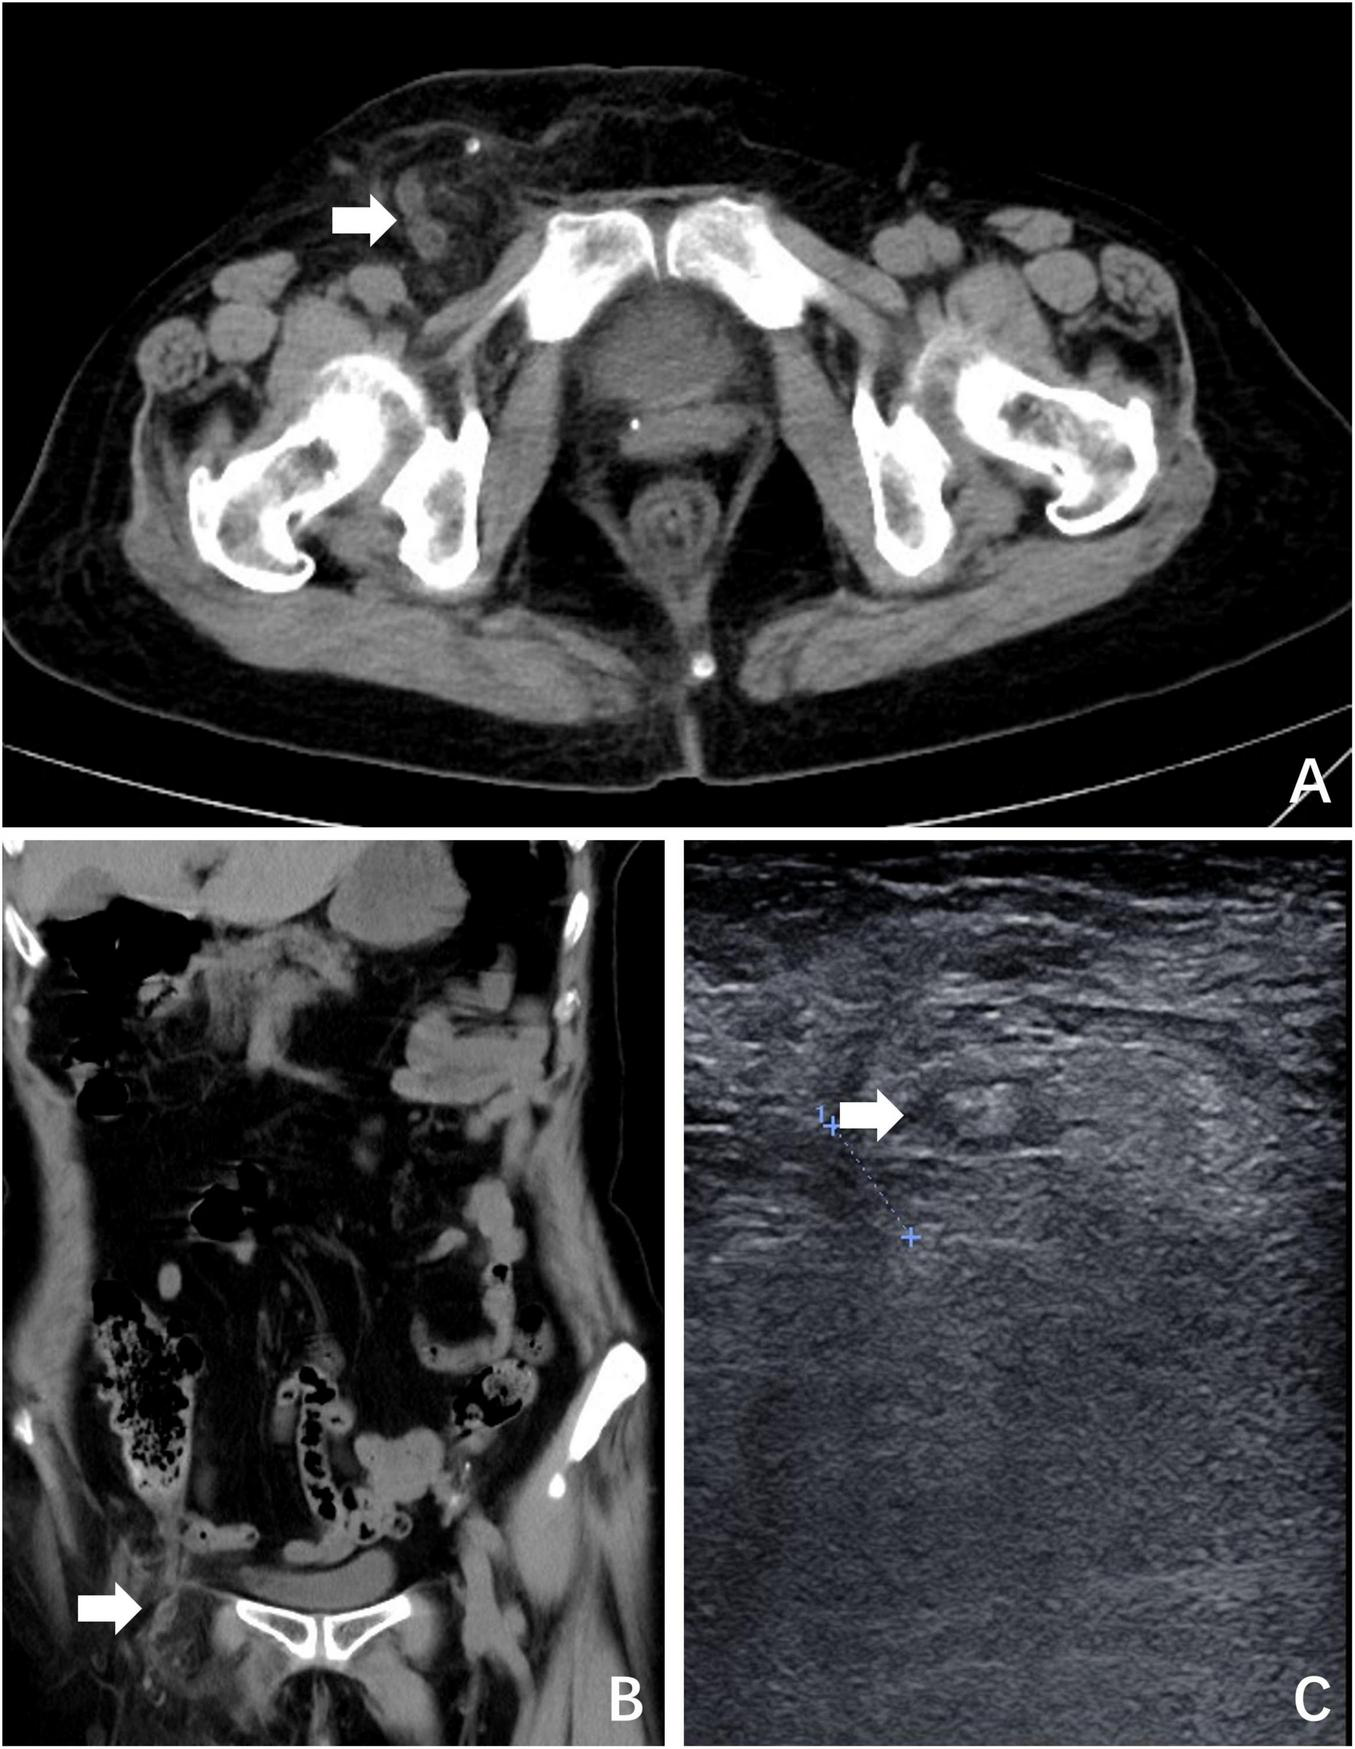

A 69-year-old woman presented with a 24-h history of right inguinal distension and pain. The patient developed a tender, irreducible bulge in the right inguinal region after heavy lifting in a forward-flexed position. She reported maintained flatus passage but denied vomiting, diarrhea, or febrile symptoms. Medical history included hysterectomy for uterine fibroids three decades prior, with no personal/family history of hernias or malignancies. Abdominal examination was unremarkable. The right inguinal area demonstrated localized erythema, warmth, and a firm 3-cm irreducible tender bulge (Figure 1). Computed tomography (CT) revealed a right femoral hernia defect inferior to the inguinal ligament and lateral to the pubic tubercle, containing the herniated appendix (Figures 2A, B). Concurrent ultrasonography identified an incarcerated right femoral hernia with a tubular structure in the sac consistent with appendiceal involvement, showing wall thickening, periappendiceal fat stranding, and increased attenuation (Figure 2C). Laboratory parameters (complete blood count, hepatic/renal function) remained within normal limits. The patient was diagnosed with De Garengeot hernia complicated by acute appendicitis.

FIGURE 2

Preoperative imaging. (A) CT revealed a right femoral hernia defect inferior to the inguinal ligament and lateral to the pubic tubercle, containing the herniated appendix (white arrow); (B) coronal plane view of CT; (C) ultrasonography identified an incarcerated right femoral hernia containing the appendix (white arrow).